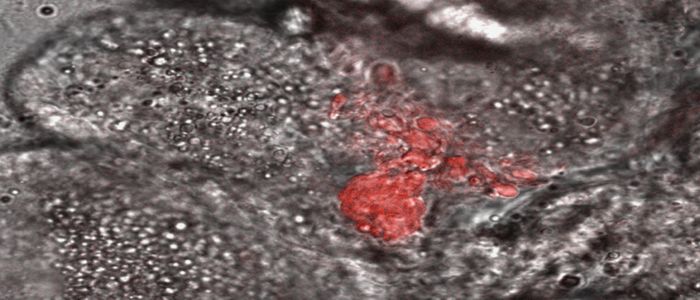

Following on from World Mosquito Day in August, we’re proud to share with you our collaborative work with research partners throughout the world to understand, treat and prevent malaria.

World Mosquito Day was established in 1897, when the link between mosquitoes and malaria was discovered by Sir Ronald Ross. It aims to raise awareness about causes and prevention. It is also a salute to the groundbreaking work of Sir Ross and scientists who have followed him.